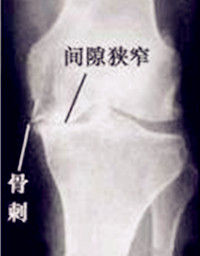

3、嚴重者膝關節腫脹,關節積液,晨僵及久坐後膠著,關節伸屈功能障礙,上下台階、久立時,膝關節症狀加重。少數病人可見關節積液,局部有明顯腫脹、壓縮現象,膝其中關節前內側條索樣腫塊伴伸膝障礙,膝關節周圍骨贅形成,關節周圍伴有骨質疏鬆與骨質硬化。

4、關節間隙變窄,關節面毛糙不平,其內側脛骨關節面受累明顯,關節間隙變窄。其中多數會發生內側間隙狹窄,髕骨骨刺形成。